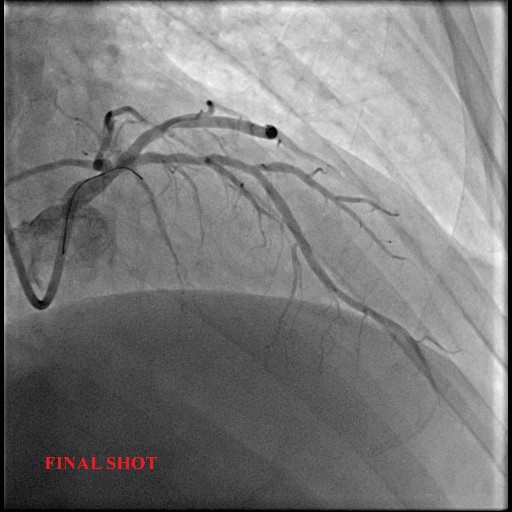

The lesion was predilated again with a 2.5x15mm and subsequently was treated with a drug-coated balloon 2.75x30mm. Final result showed good luminal gain and TIMI 3 flow.

A 58-year-old man with underlying hypertension presented with chest discomfort during exertion and a positive stress test. Echocardiogram shows ejection fraction of 54% and no regional wall motion abnormalities. He underwent a coronary angiogram which showed severe stenosis of the proximal LAD and moderate disease of Left main stem. We proceeded with PCI of the proximal LAD using a drug-coated balloon (DCB). The final angiography showed TIMI 3 flow.